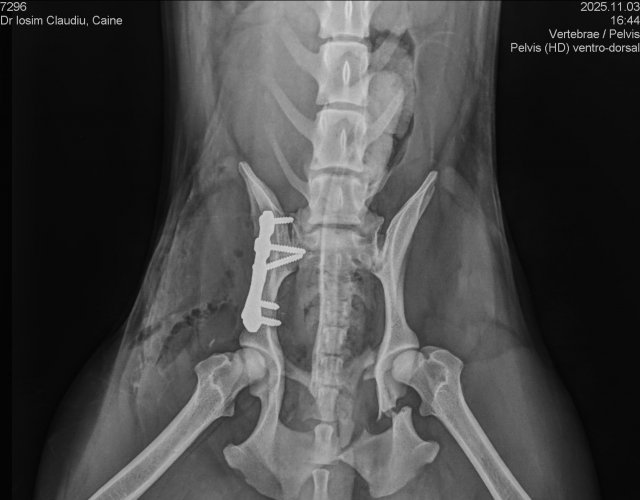

Caine accidentat

Asistență medicală -

O doamna a gasit un caine lovit de masina si l-a tras pe marginea drumului pentru a suna peste tot in cautare de ajutor. Am raspuns pozitiv si am facut totul pentru el. Din pacate nu a putut fi …